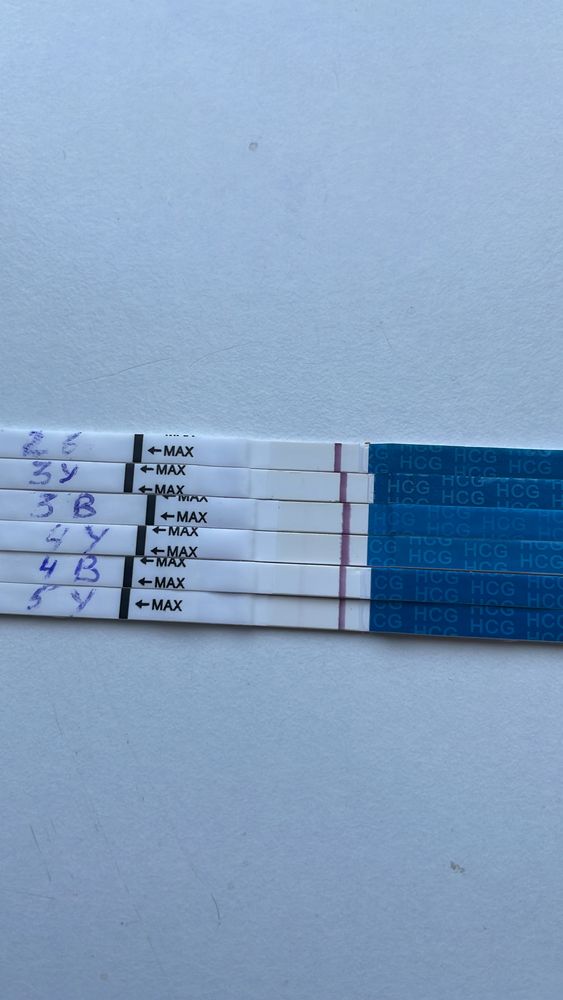

Всем привет) Реву, не могу. Подскажите стоит ли надеяться на что-то? Хгч на 7дпп-82 (инвитро), 9 дпп-137 (целди) и 13 дпп - 512 (инвитро).

Девочки тут на ваш глаз сколько единичек хгч может быть? Тесты мама чек